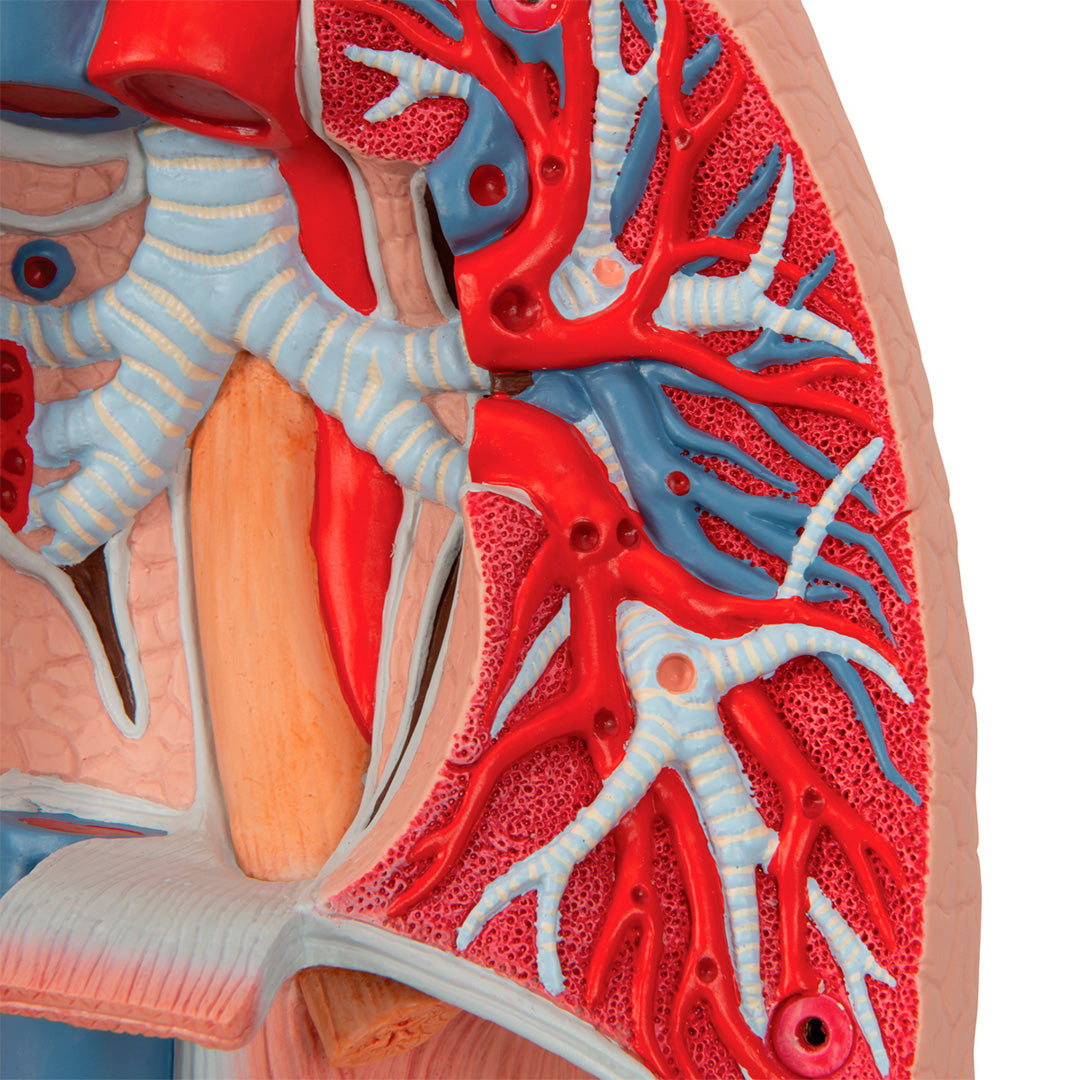

Modelo del pulmón, 7 piezas

Modelo del pulmón, 7 piezas

Descripción

Una sección aumentada y muy detallada a través de la mitad derecha del encéfalo, incluyendo una porción del cráneo.

Tiene dos lados y está coloreado delicadamente.

El modelo incluye 49 referencias, identificables en las indicaciones en inglés.